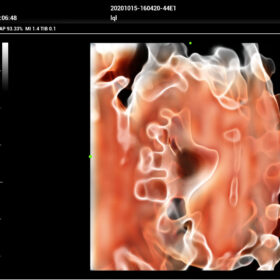

Comprehensive Imaging Solutions Powered by ZST+

The ZST+ platform is a remarkable advancement, marking a significant evolution in ultrasound technology. It revolutionizes the processing of ultrasound metrics, moving away from the traditional beam-forming approach to channel data-based processing. This breakthrough eliminates the longstanding trade-off challenges between spatial resolution, temporal resolution, and tissue uniformity. The result is outstanding image quality, providing limitless imaging solutions with continuous enhancements.

- Smart Scene 3D – Full Stack smartness obstetric solution empowered by ZST+. Comprehensive 3D/4D OB imaging solution with comprehensive fetal parts coverage.